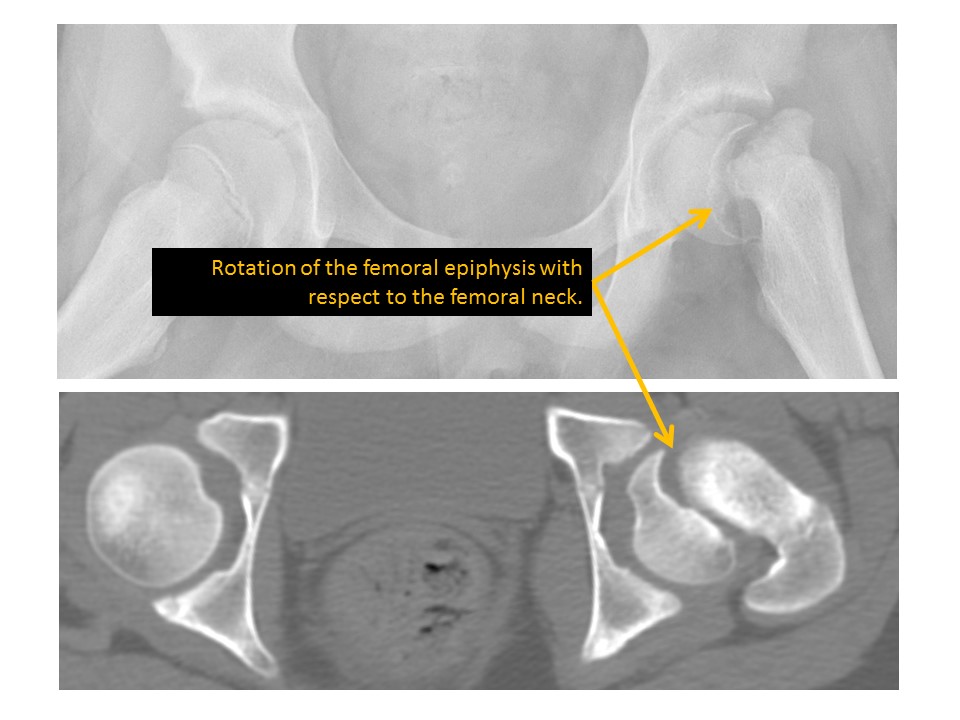

There is slipped capital femoral epiphysis. [Yes/No]